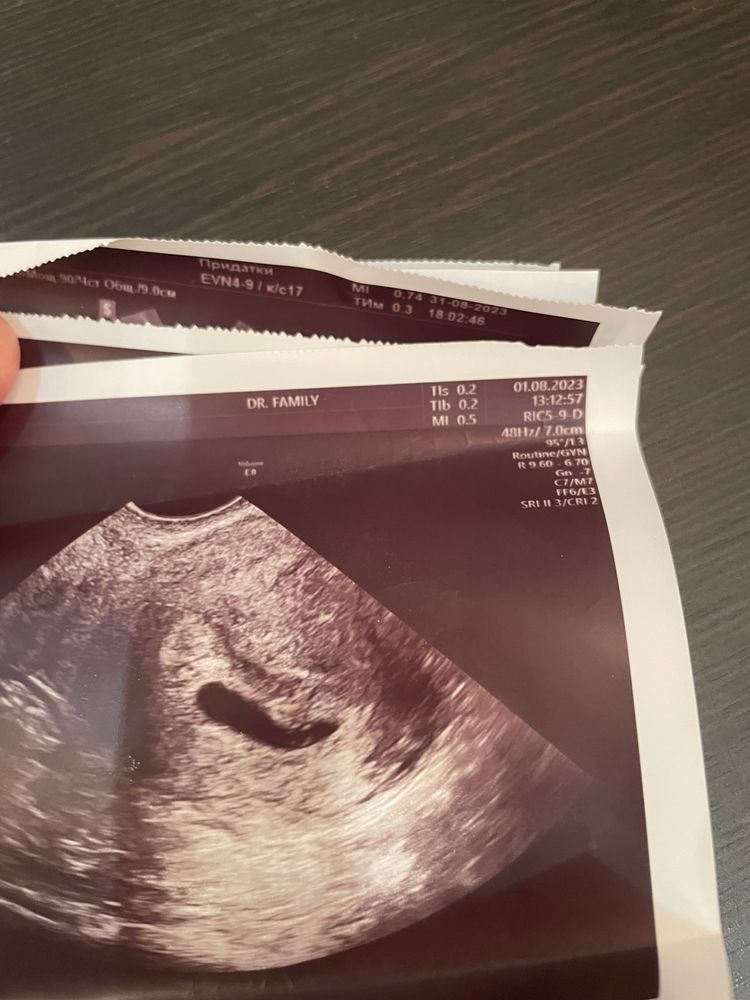

Малый срок беременности,плодное яйцо не круглое

Изображение Изображение У меня так же было , напугали до смерти только , бесячие врачи 😄все хорошо будет

Натали , ого,а у меня как груша форма была

Amina, ну вот , а у меня вообще червяк какой то 😂😂😂его всего расплющило как могло , думаю из за тонуса , потому что мазать начало еще коричневым потом и живот болел как при месячных , ну я и натерпелась тогда 😩😬 сейчас у нас все прекрасно 🩷 и вас тоже все будет хорошо !! ☺️😉